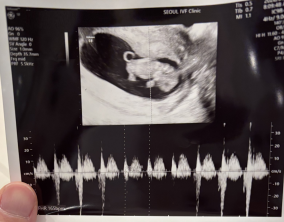

임신 수치 16, 9주차 기적의 기록